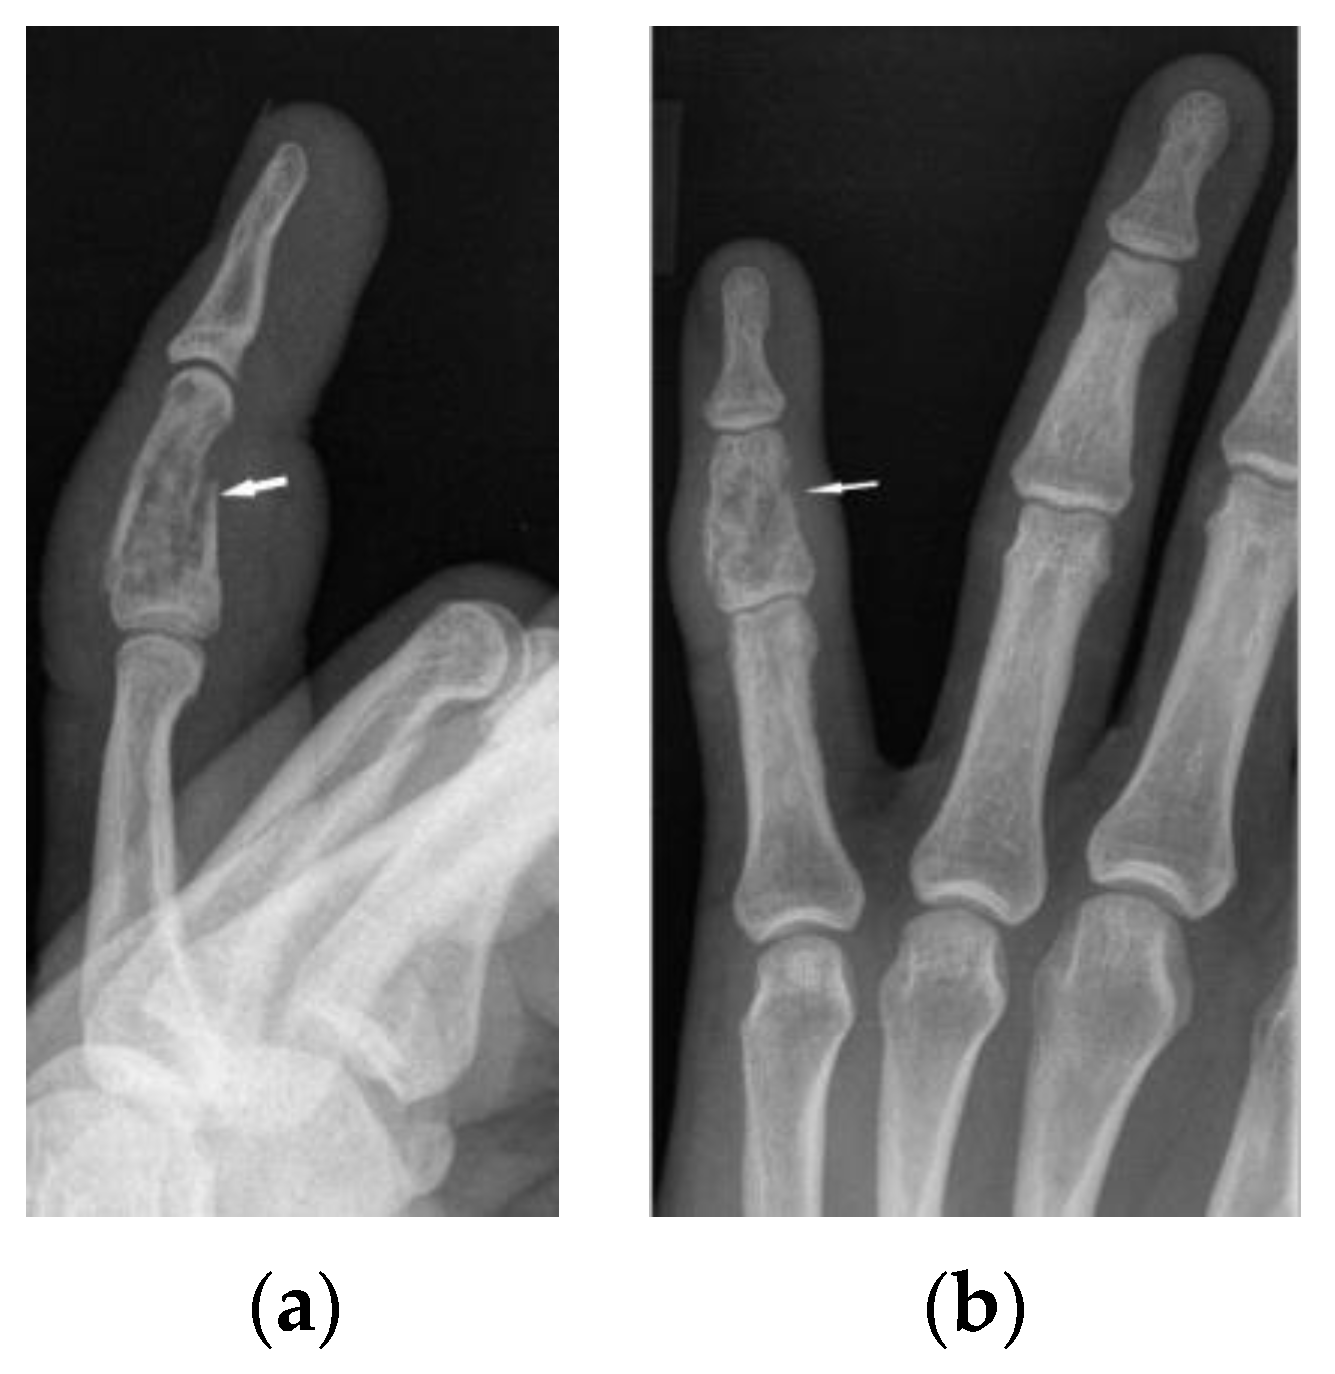

The radiographic appearance of phalanges occupied by sarcoidosis includes lytic lesions of various sizes, called cysts. Cystic lesions, mostly punched-out, may be accompanied by soft tissue nodules. The presence of large cysts increase the risk of pathological bone fracture [20] (Figure 6a,b). Numerous small cysts are more frequently observed. The articular surfaces are preserved, although cysts located in the subchondral layer might mimic erosions (Figure 7). Periosteitis is uncommon.

Features of bony destruction may be permeative and cause scalloping of the cortex, whereby cortical margins are preserved. Bone destruction with moth-eaten pattern may involve the cortex, usually with associated soft tissue swelling [19]. The cortical and trabecular architecture is usually remodeled [20]. The phalanges of the second and third fingers of the hand are most often involved, leading to the image of sausage-shaped fingers [20].

Figure 6. X-ray of the left hand, lateral view (a), PA (b). Osteolytic pattern in the middle phalanx with pathological fracture (white arrows). Soft tissue swelling.